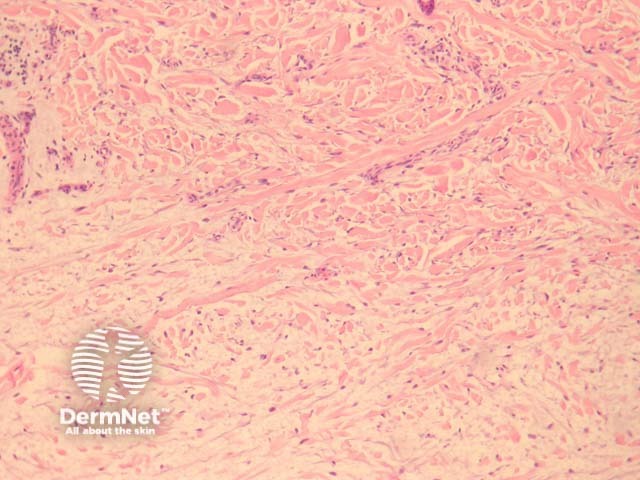

There are deposits of mucin throughout the dermis accompanying by fibroblast proliferation and collagen deposition (figure 1, 2).

The fibroblast proliferation may be more overt with generalised scleromyxoedema.

Figure 1